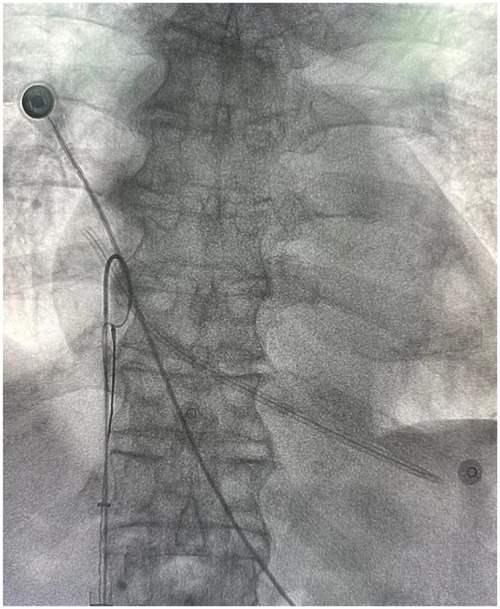

Background: With the advancements in endovascular techniques, reports of rare vascular complications have increased. This case describes the accidental fracture of a non-cuffed hemodialysis catheter and its subsequent endovascular management, offering valuable insights for the treatment of similar intravascular foreign bodies (IFBs). Case Report: An 83-year-old male with a non-cuffed catheter presented after a catheter fracture. Radiographic imaging confirmed migration of the fragment to the right atrium. After a multispecialistic collaboration assessment, endovascular retrieval was performed via right femoral access using a filter retrieval device under fluoroscopic guidance. The catheter fragment was successfully captured and removed without procedural complications. The patient recovered uneventfully and remained well at follow-up evaluations. Conclusion: This case highlights the efficacy and safety of percutaneous endovascular retrieval for managing IFBs, providing a minimally invasive alternative to surgery with high success rates. Meticulous catheter handling and regular integrity assessments are critical to prevent and promptly manage such events.